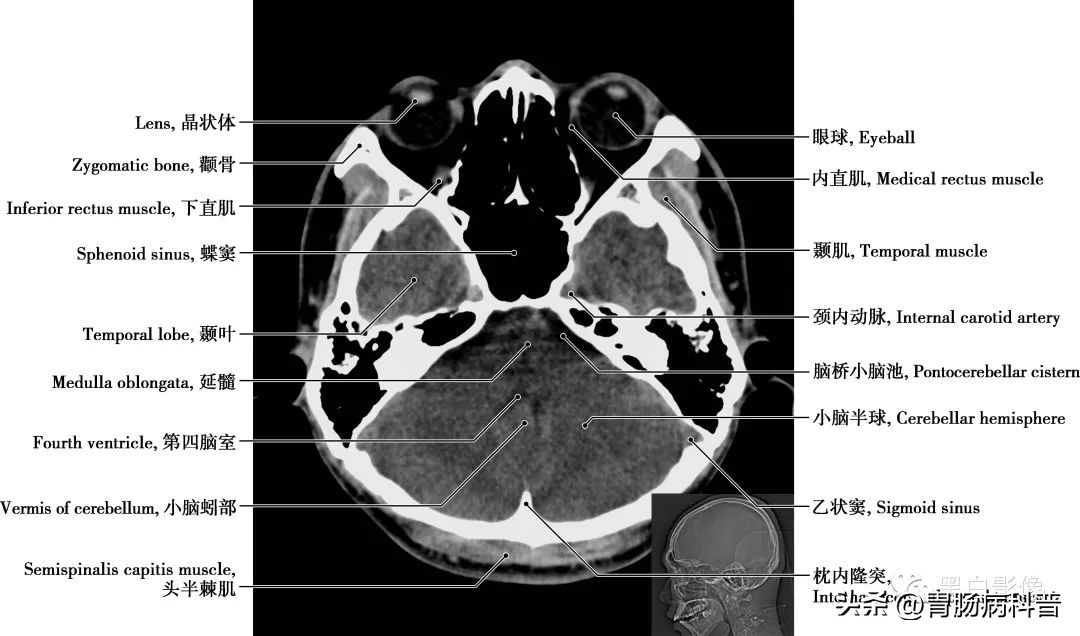

图1-1-14 经第四脑室中央轴位切面

脑桥 位于延髓上方,腹面膨大的部分为脑桥基底部,基底部向两侧变窄,称脑桥臂,与后方小脑相联系。基底部外侧有三叉神经出脑,横沟里由内向外依次有展神经、面神经和位听神经,有调整呼吸、调节肌肉运动等功能